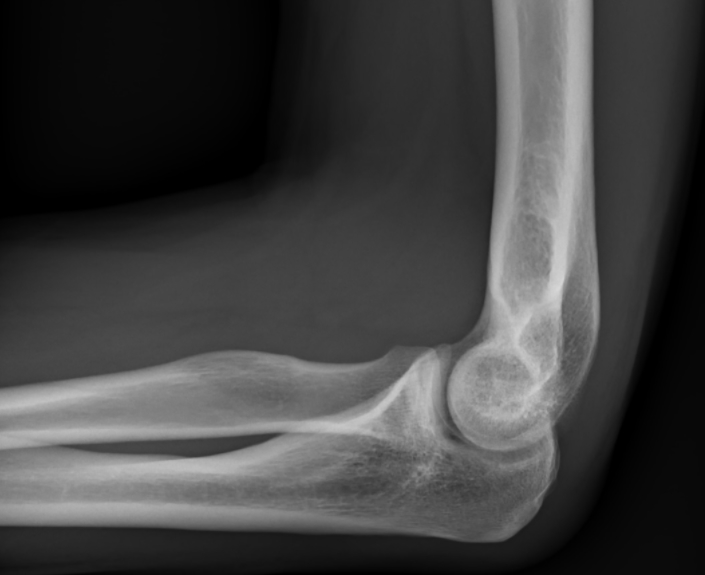

4. 구부리고 펼 때 팔꿈치 통증

변형성 팔꿈치 관절증이 원인일 수 있습니다. 팔꿈치를 완전히 펴거나 완전히 구부리기 힘든 경우, 팔꿈치를 움직일 때, 새끼손가락과 약지가 저릴 때, 가끔 잡아당기는 듯한 심한 통증 등이 나타납니다.